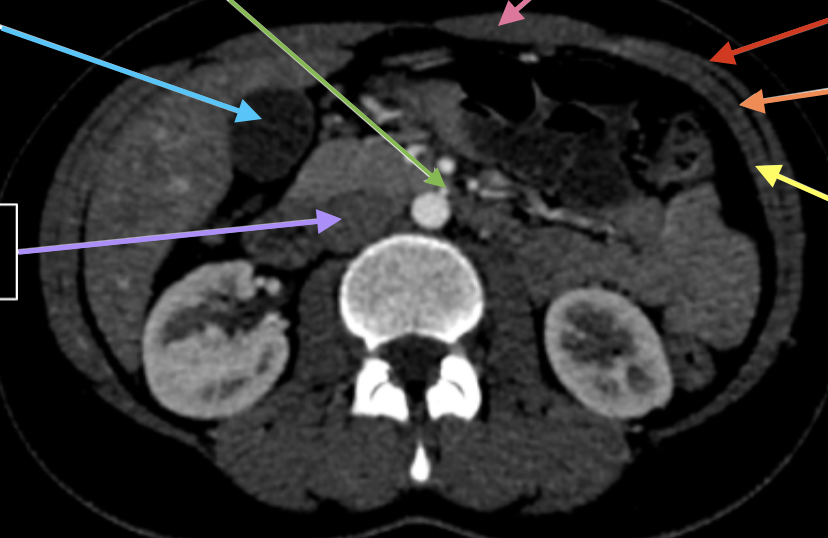

Hepar

knowt flashcard image

2

New cards

aorta abdominalas

3

gaster

4

splen

5

truncus coeliacus

rosa

6

a gastrica sinistra

blå

7

v splenica

röd

8

ren sin

grön

9

a hepatica communis

10

a mesenterica superior

orange

11

a splenica

12

lila

13